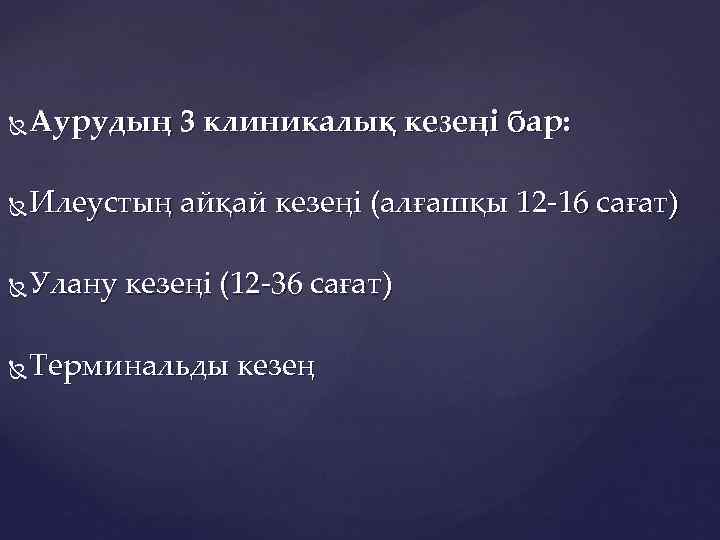

Аурудың 3 клиникалық кезеңі бар: Илеустың айқай кезеңі (алғашқы 12 -16 сағат) Улану кезеңі (12 -36 сағат) Терминальды кезең